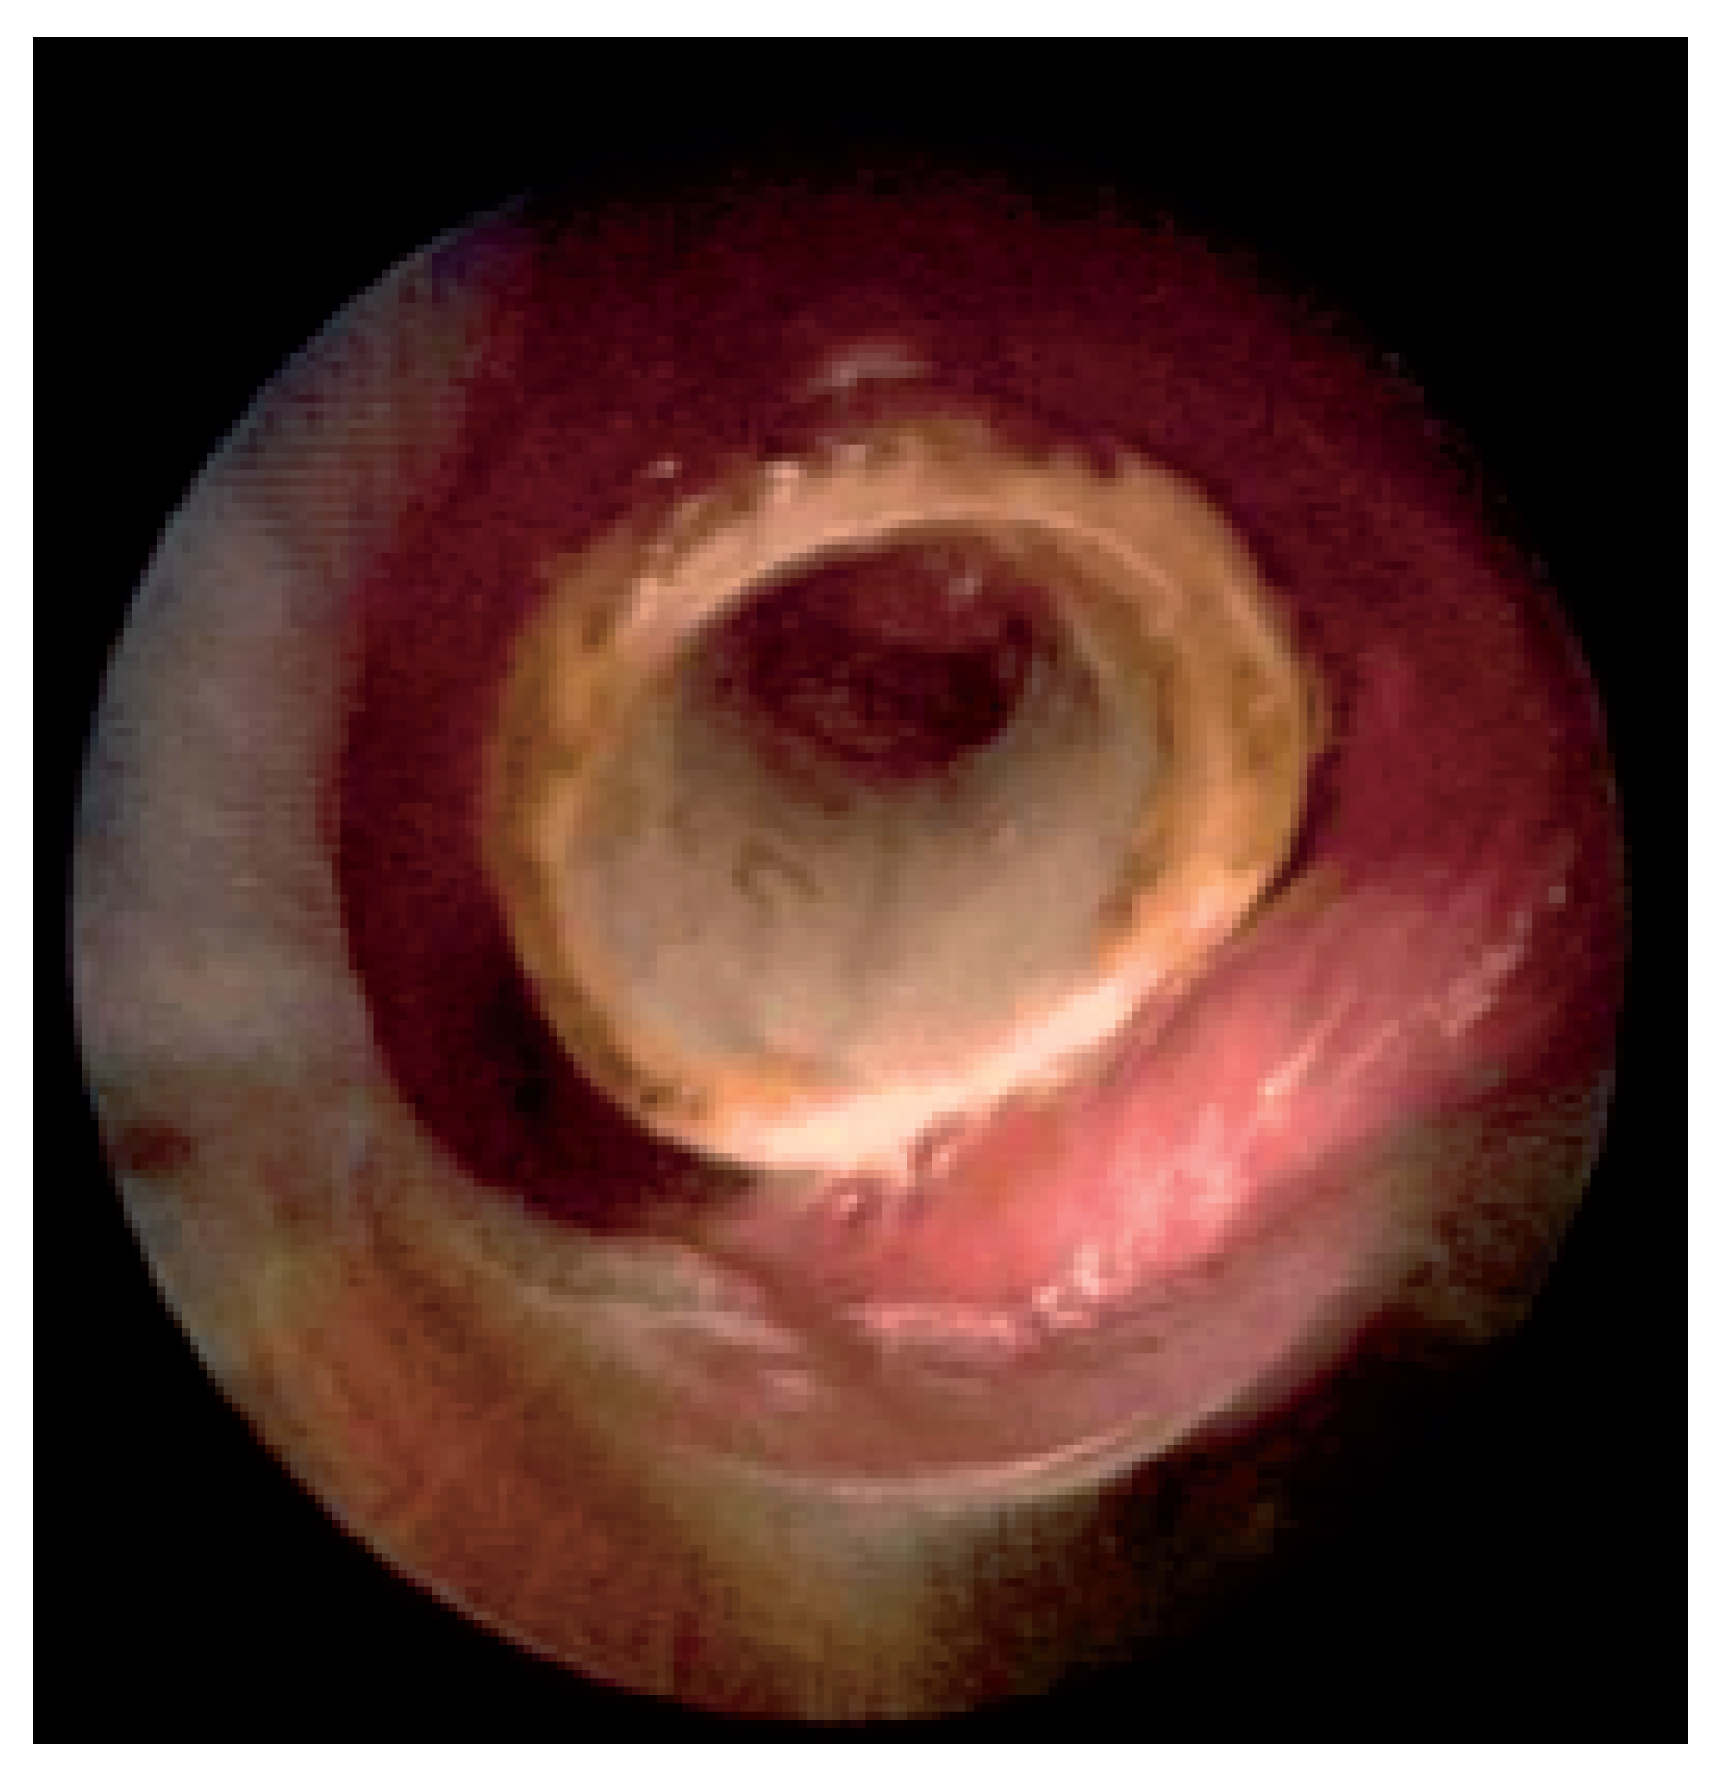

Abbildung 1. Hochgradige Trachea-Stenose beim Plattenepithelkarzinom. Der Pfeil markiert das freie Lumen.